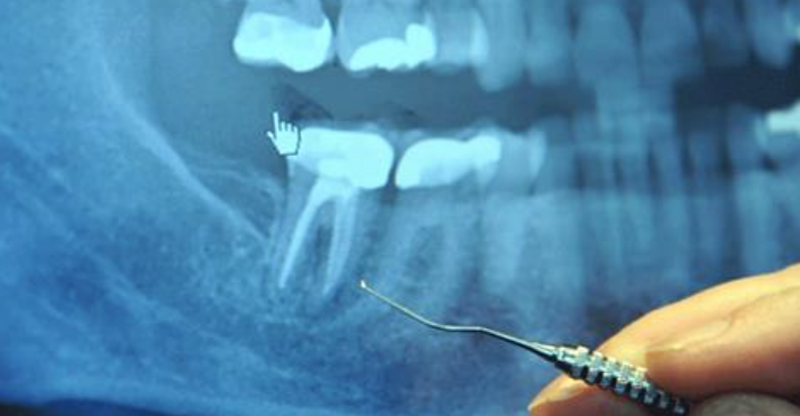

The roots of each tooth descend into your jawbone and are held in place by the periodontal ligament. In dental school, dentists are taught that each tooth has one to four major canals. However, there are accessory canals that are never mentioned. Literally miles of them!

Just as your body has large blood vessels that branch down into very small capillaries, each of your teeth has a maze of very tiny tubules that, if stretched out, would extend for three miles. Weston Price identified as many as 75 separate accessory canals in a single central incisor (front tooth). For a more detailed explanation, refer to an article by Hal Huggins, DDS, MS, on the Weston A. Price Foundation website.

When a dentist performs a root canal, he or she hollows out the tooth, then fills the hollow chamber with a substance (called guttapercha), which cuts off the tooth from its blood supply, so fluid can no longer circulate through the tooth. But the maze of tiny tubules remains. And bacteria, cut off from their food supply, hide out in these tunnels where they are remarkably safe from antibiotics and your own body’s immune defenses.